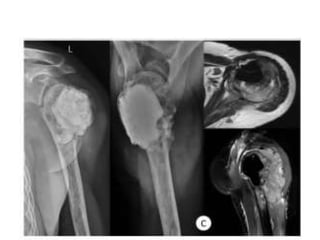

JULY 2009

SEPT 2009

1 year later

AUG 2010

JAN 2013

• MAY 2013

• DENOSUMAB started

• 360 mg subcutaneous dose

• Followed by 120 mg every month

OCT 2013

• Pain around knee joint diminished

• Further resection ??

• Patient refused

• Clinical improvement persisted until jan 14

• Presented with Rapidly growing painful

palpable mass

• Open biopsy : high grade sarcoma

• A/K amputation